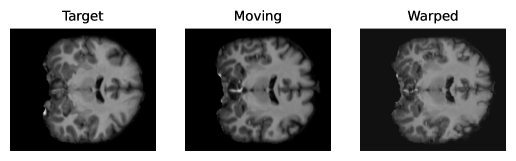

Figure 3 shows qualitative results generated for the NLST and OASIS datasets. Table 2 summarizes the results when comparing RWCNet with LAPIRN on the NLST and OASIS datasets. RWCNet outperforms LAPIRN on both datasets. However, the difference in Dice is only 0.7%, which might be entirely explainable by random weight initialization in network training. For the NLST dataset, the difference in performance is much more pronounced, with the difference in average TRE being 3mm. These results suggest that the architectural features of RWCNet, significantly aid generalization performance in the more challenging large-displacement setting.

| (a) OASIS sample results |